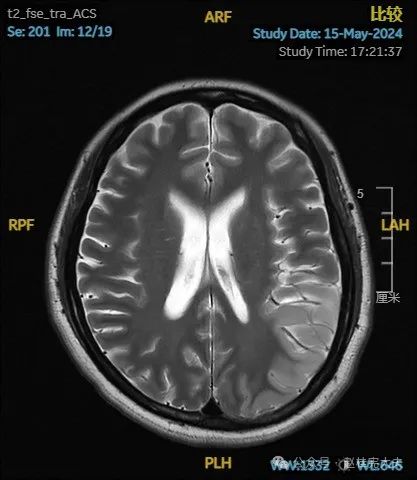

入院后给予精氨酸,左卡尼丁,辅酶Q10,维生素E等治疗。患者病情稳定好转中,2天后意识清楚,语言表达仍欠佳。当天复查颅脑磁共振如下:

以上为患者发病后3次的颅脑磁共振片子,临床诊断基本上可以确认了,希望患者逐渐恢复!